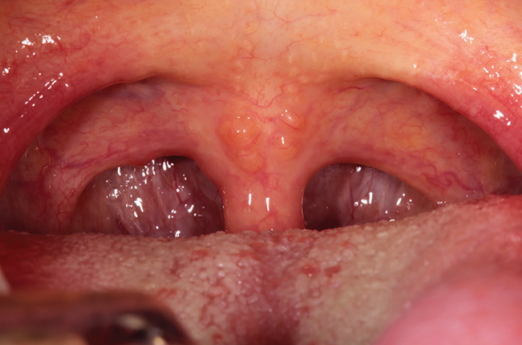

Estomatitis por Nicotina